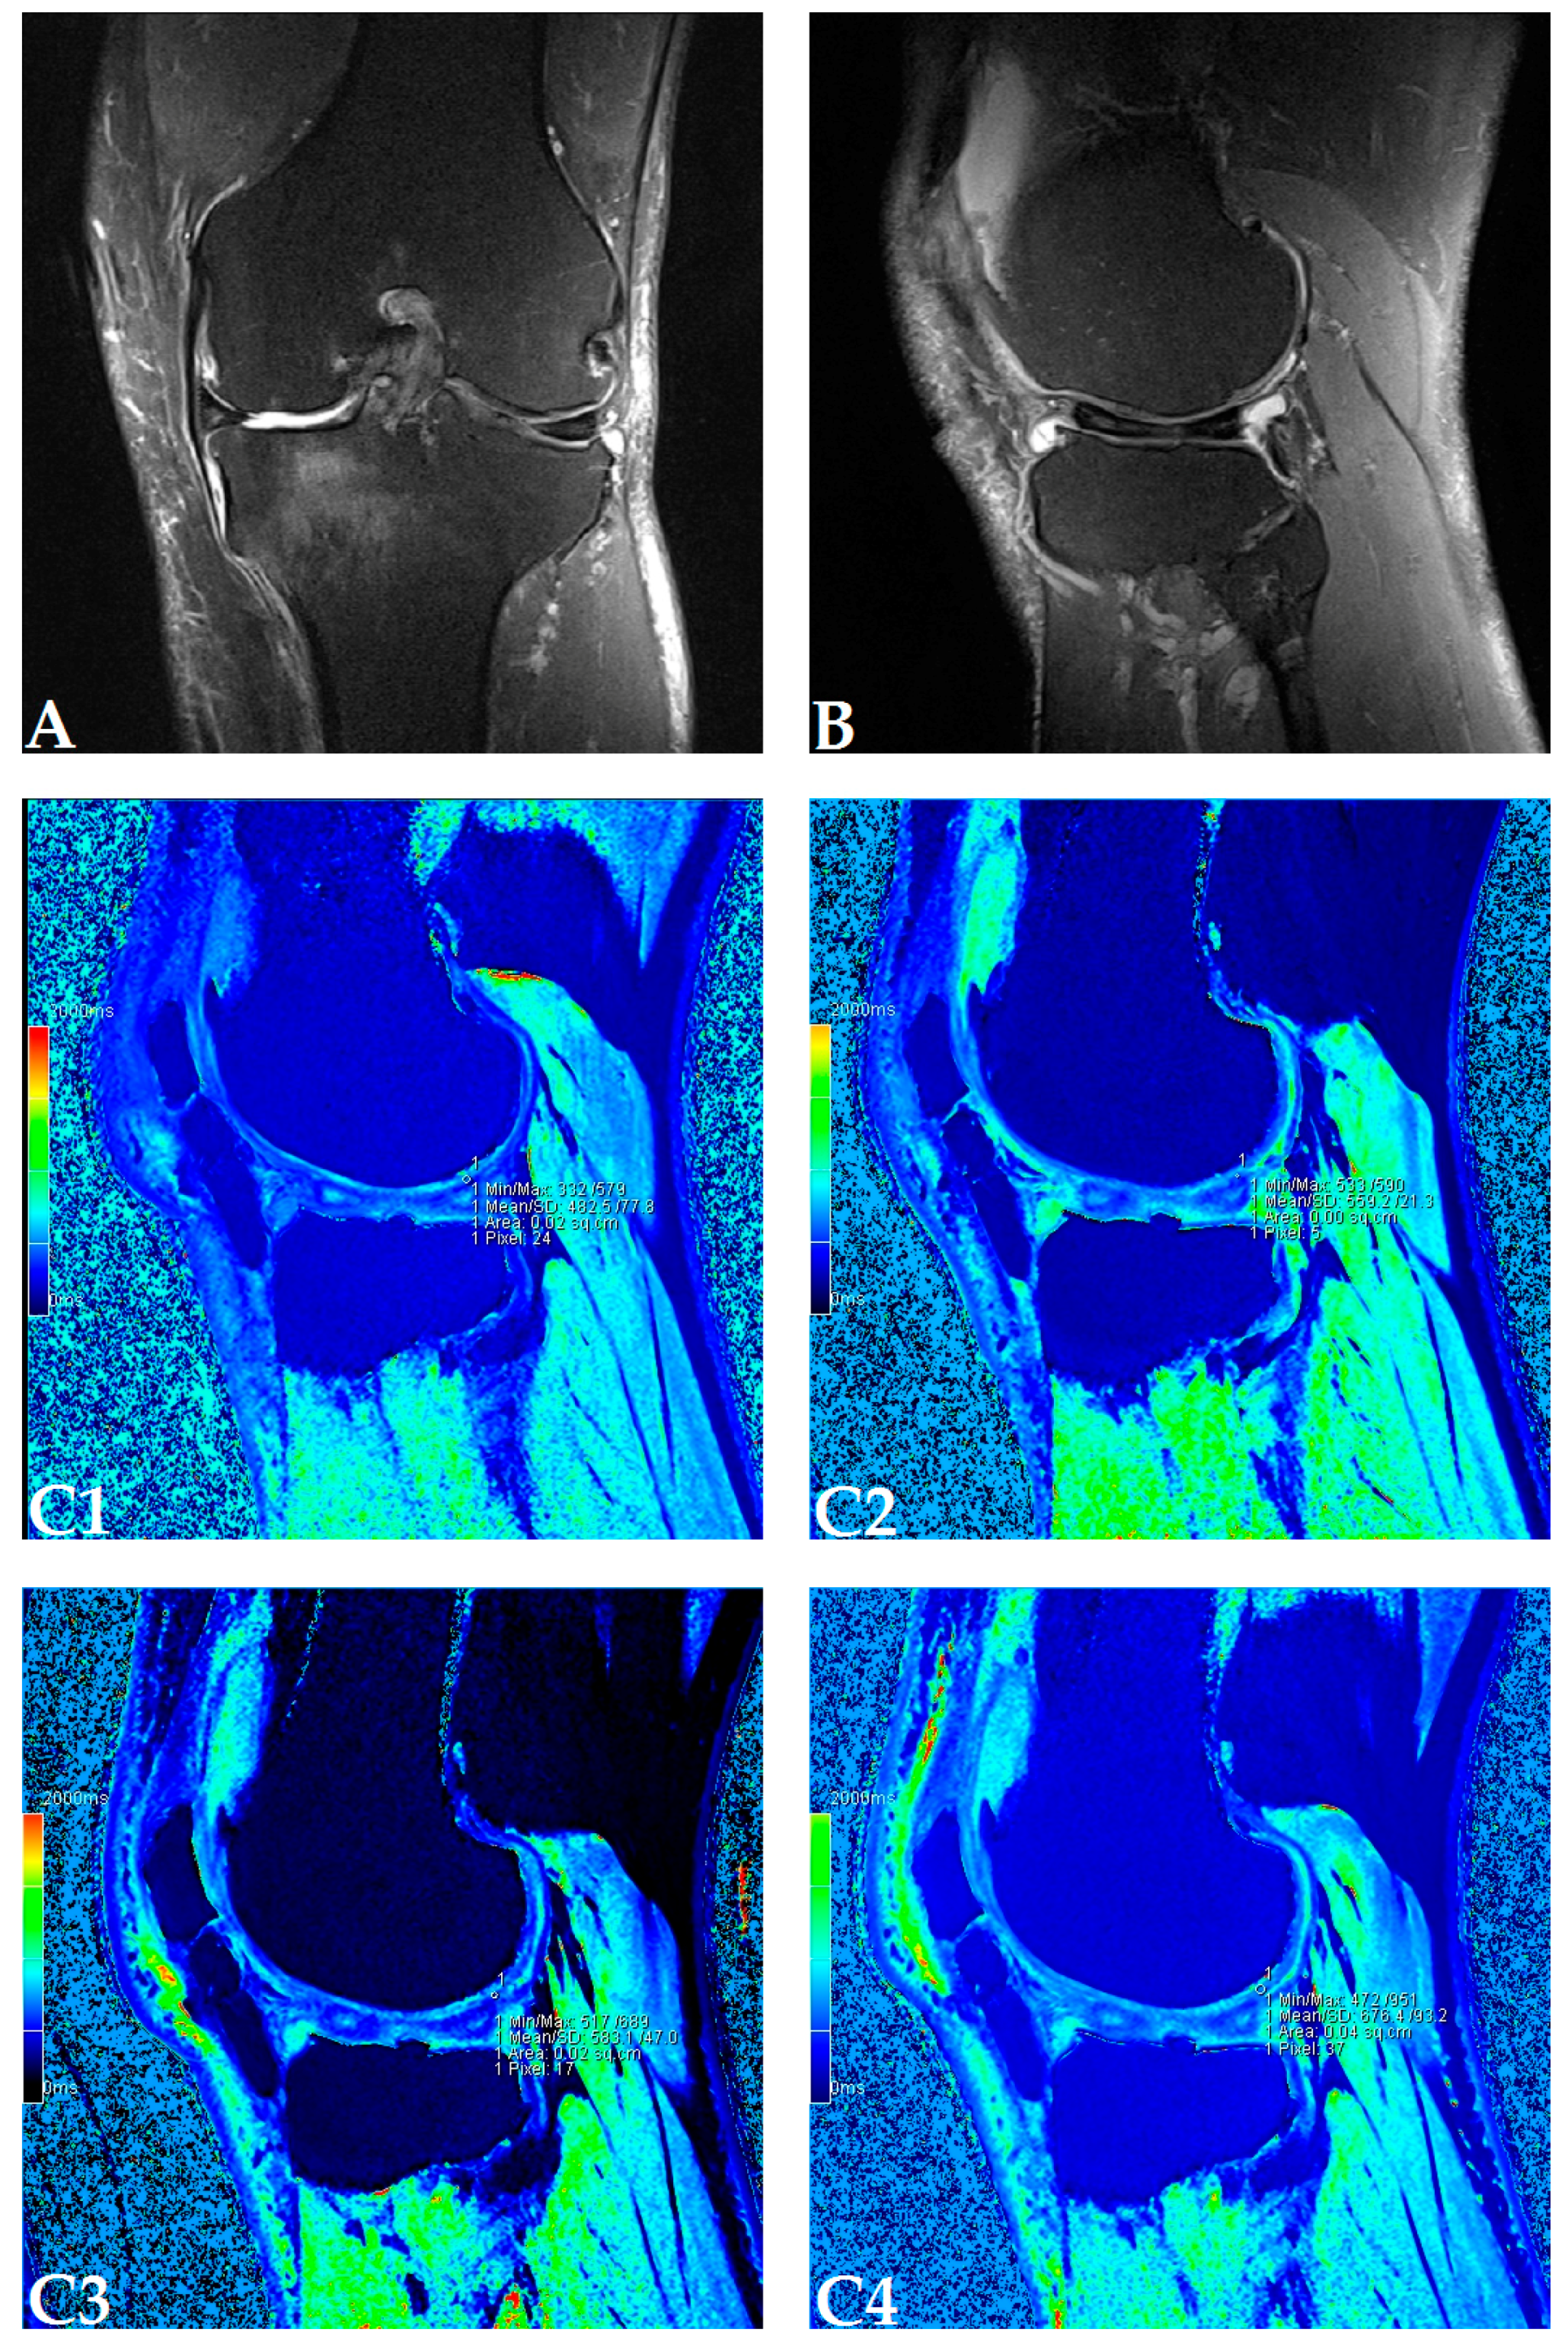

The dGEMRIC index was measured on seven different articular facets for each knee in the study, and the results are presented in a separate table for each patient (Supplementary Figures S1–S18). The dGEMRIC index was presented in absolute values, and the change of the index value through the study period is shown in percentages in relation to the baseline dGEMRIC index value. However, we observed that there was an increase in index value for the most articular facets after autologous and microfragmented adipose tissue injection. In 120 (53.57%) of 224 joint facets, we observed an increased dGEMRIC index 12 months after autologous and microfragmented adipose tissue injection. As expected, in cartilage lesions International Cartilage Repair Society (ICRS) grade IV, there were no changes in dGEMRIC value through the study period. In 33 (14.73%) joint facets, a decreased dGEMRIC index was found after 12 months in comparison with the baseline. Only in four (1.7%) of those was the decrease greater than 15% (highest in patient dG14, Figure S12). Those were joint facets with ICRS grade III and IV chondromalacia. For example, in patient dG15 (Figure 1D) with 4.4° varus deformity of the left knee, there was a 45% dGEMRIC index increase of the left lateral femoral condyle and an 83% index increase of the left lateral tibial condyle in comparison with the baseline. We also observed an increase of 13% and 3% for the lateral and medial patellar facet, respectively. However, the femoral trochlea index decreased by 4%. In patient dG07 (Figure 2D) with varus knee deformity (left knee 9.8° and right knee 3.5°), we observed a 26% increase of the index value in the medial condyle of the right tibia at the end of the study. Similarly, elevation was observed in other areas.

Figure 1.

(Patient dG15) Coronal (A) and sagittal (B) magnetic resonance (MR) images show complete loss of articular cartilage of the medial femoral and tibial condyles (International Cartilage Repair Society (ICRS) grade IV chondromalacia), thinning and shallow fissures of the articular cartilage in the lateral femoral and tibial condyles (ICRS grade IV chondromalacia), edge osteophytes and joint effusion. MR images with the dGEMRIC index values at four-time points (T0: baseline, T3: three months after autologous and microfragmented adipose tissue injection; T6: six months after autologous and microfragmented adipose tissue injection; T12: 12 months after autologous and microfragmented adipose tissue injection) (C1–C4). The scheme of the dGEMRIC index with different joint facets throughout the study period at T0, T3, T6 and T12 combined with visual analogue scale (VAS) ratings at T0, T3, T6, T12 (D).